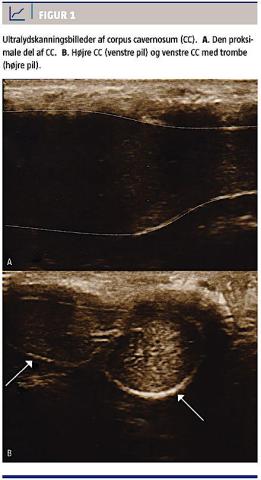

En 70-årig mand blev indlagt på en urologisk afdeling med anæmi (hæmoglobinniveau 3,9 mmol/l) og symptomer i form af svær træthed, men var dog oppegående og uden øvrige anæmisymptomer. Han havde ni måneder tidligere fået diagnosen blærecancer, som på diagnosetidspunktet var dissemineret til bækken og rygsøjle og blev behandlet med transuretral resektion af patologisk væv i blæren, palliativ strålebehandling mod blæren og palliativ kemoterapi. Efter transfusion med seks portioner SAG-M over et døgn fik patienten smerter i perineum og proksimalt i penis. Begge steder kunne et hævet og smertefuldt område, som ikke var til stede ved indlæggelsen, palperes. Patienten havde ikke været udsat for traumer mod penis og fik ingen medicinsk behandling, som kunne tænkes at disponere for PP. Fire dage efter symptomdebut fik han pga. fortsatte smerter foretaget ultralydskanning med farve-Doppler af penis, hvorved man påviste en forstørret, blodfyldt (erigeret) proksimal CC uden blodgennemstrømning

(Figur 1). Ved den distale afgrænsning af dette område kunne der ses en trombose. Ved en CT to måneder tidligere havde man ikke i det lille bækken påvist tumorer, som kunne afklemme det venøse tilbageløb. Patienten kunne smertedækkes sufficient med paracetamol og tramadol og blev sat i behandling med lavmolekylært heparin (LMWH) 12.500 IE en gang dagligt i tre måneder med henblik på opløsning af trombosen. Ved kontrol ti uger efter påbegyndelsen af af LMWH-behandlingen var den partielle erektion væk, ligesom ømhed og smerter var forsvundet. Patienten havde i årevis lidt af komplet erektil dysfunktion, hvorfor den erektile funktion efter endt behandling ikke kunne vurderes.